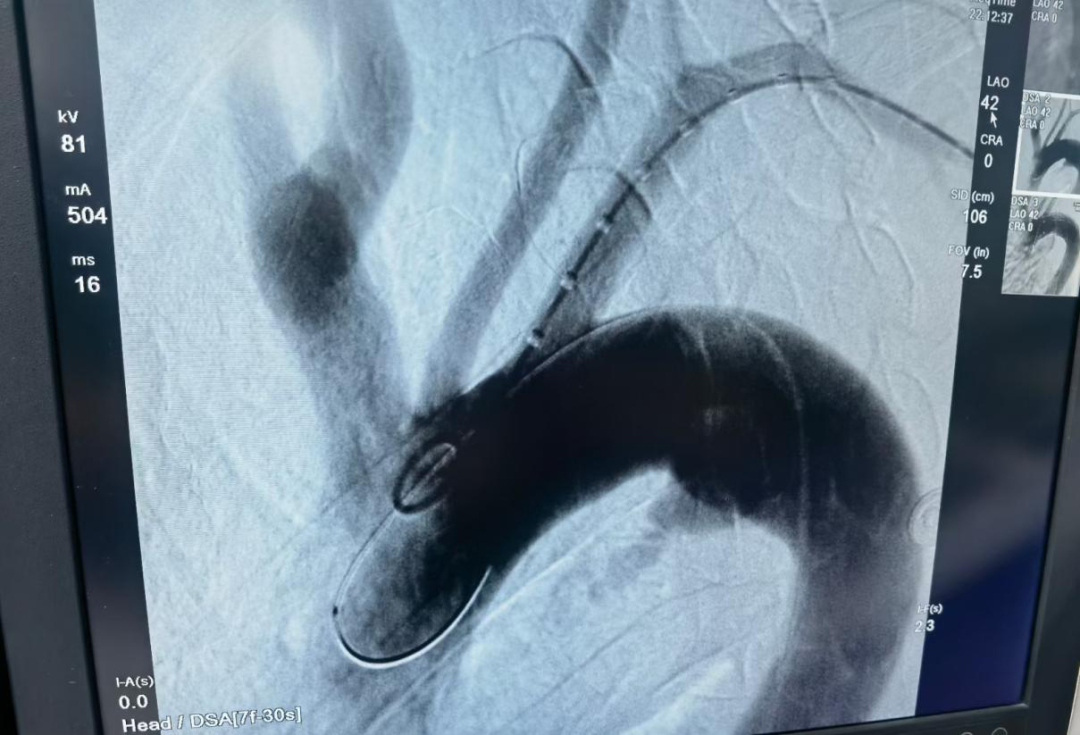

晚9時許,在心內(nèi)科、介入科以及家屬的積極配合下,血管外科團(tuán)隊(duì)開始為患者在局麻下行主動脈瘤體破裂腔內(nèi)隔絕術(shù),憑借著精湛的技藝和團(tuán)隊(duì)成員間嫻熟的配合,短短半個小時,手術(shù)成功結(jié)束,主動脈瘤破口封堵,患者血壓平穩(wěn)。

▲支架植入前造影,瘤體顯影。

▲支架植入后,假性動脈瘤未顯影,腔內(nèi)隔絕良好。